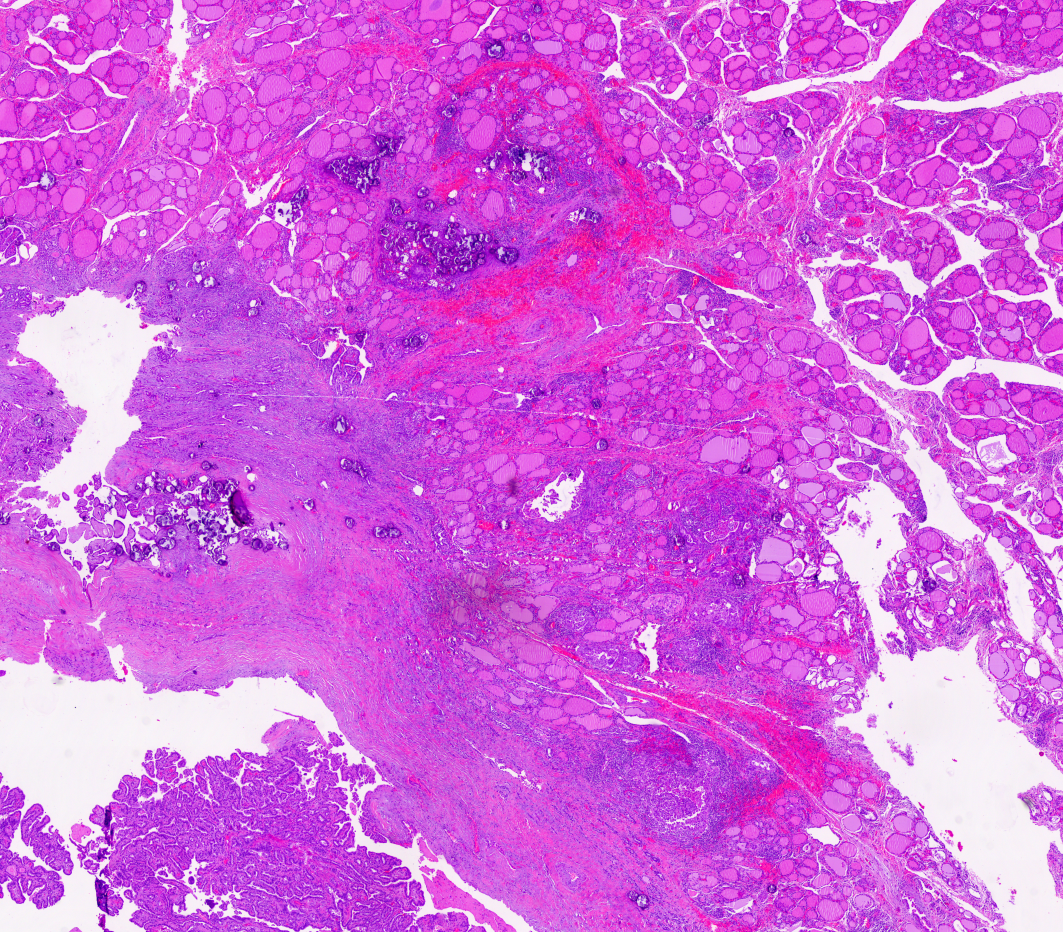

Cribriform-morular thyroid carcinoma Tiroidin nadir tümörü. Belirsiz papiller yapılar, moruller ve tiroglobulin yokluğu. Beta katanin ilişkili.

Cribriform-morular thyroid carcinoma, ikinci odak ile birlikte Çok sayıda odak içeren tümörde iki ayrı tümör odağı